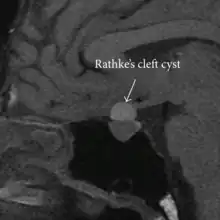

| Rathke's cleft cyst in a 53-year-old man with a pituitary adenoma and acromegaly |